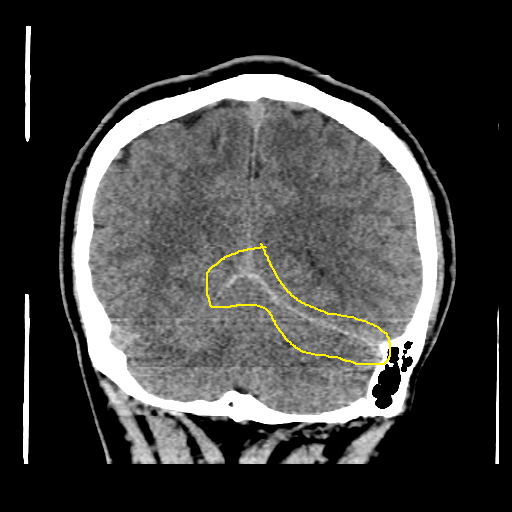

16살 환자의 brain CT를 보도록 하자.

어린 나이라 나이든 사람의 brain CT보다 뇌 실질 자체의 부피가 크고 빈 공간이 적어 보이게 된다.

사람의 두개골 내에는 대뇌와 소뇌, 그리고 좌우 반구를 나누는 얇고 넓은 막이 있다. 좌우 대뇌를 나누는 구조물을 falx cerebri 라고 하며, 대뇌와 소뇌를 나누는 구조물을 tentorium cerebelli라고 한다.

위에 16살 환자의 경우 대뇌와 소뇌를 나누는 격벽 구조를 따라 뇌출혈이 발생한 경우이다.

다행히 예후가 나쁘지는 않지만, 출혈량이 늘어나는지 확인할 필요는 있기에 입원이나 단기간 외래 추적관찰이 반드시 요구되는 상황이다.